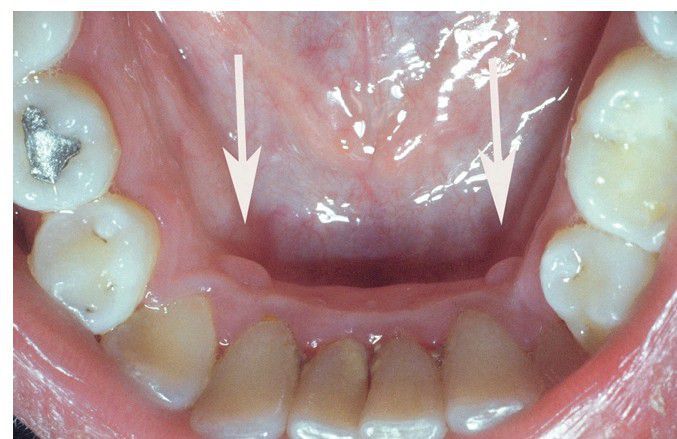

Retrocuspid Papilla

. Bilateral papular lesions on the gingiva lingual to the mandibular canines.